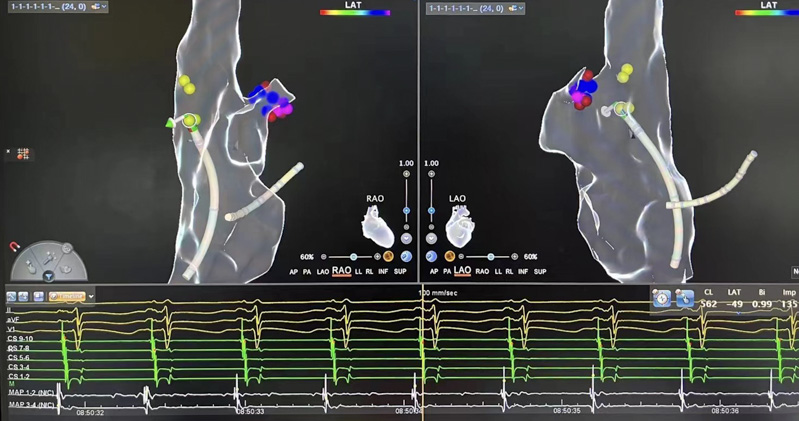

▲術(shù)中測標(biāo)

介入室內(nèi),心血管內(nèi)科電生理團(tuán)隊(duì)開始為患者進(jìn)行心電生理檢查,在三維系統(tǒng)指引下行激動(dòng)標(biāo)測提示心律失常起源于右心耳根部。右心耳是右心房的盲端,非常菲薄,大約只有1-2mm,附近有竇房結(jié)、上腔靜脈等重要結(jié)構(gòu),在此處消融,有心臟穿孔、損傷竇房結(jié)導(dǎo)致心臟停搏等風(fēng)險(xiǎn)。

劉艷麗主任綜合評估后,憑借著高超的技巧,果斷為患者進(jìn)行射頻消融,最終患者心動(dòng)過速中止,即刻恢復(fù)竇性心律。